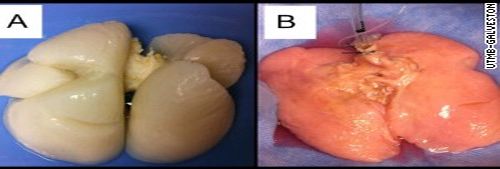

이번 연구팀의 니콜라스 박사는“교통사고로 사망한 두 명의 소년의 폐에서 콜라겐과 엘라스틴의 ‘Scaffolding(인체기관의 구조를 이루는 뼈대)’만 남기고 모든 부분을 제거한 후, 다른 폐에서 채취한 세포를 그 Scaffolding에 주입했다.

그다음으로 복제 액체(resembling Kool-Aid)로 채워진 체임버(Chamber)에 집어넣은 후, 그 세포들이 성장하여 배양되도록 영양분을 공급했다.

4주 후에 인간의 폐와 비슷한 색과 모양의 인공 폐가 만들어졌고 그러한 실험은 계속 반복적으로 이루어졌다.